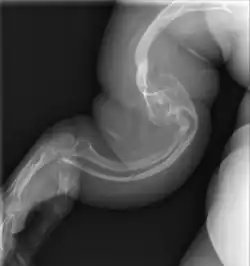

| II | Enfermedad de Vrolik, autosómica recesiva. Se caracteriza por fragilidad ósea extraordinaria, culmina en la muerte en el periodo perinatal o comienzos de la lactancia, huesos largos muy fragmentados (fémur en acordeón), prominencia de hueso parietal y temporal con occipucio colgante y osificación de cráneo retrasada extraordinariamente. |

_of_right_femur.png)